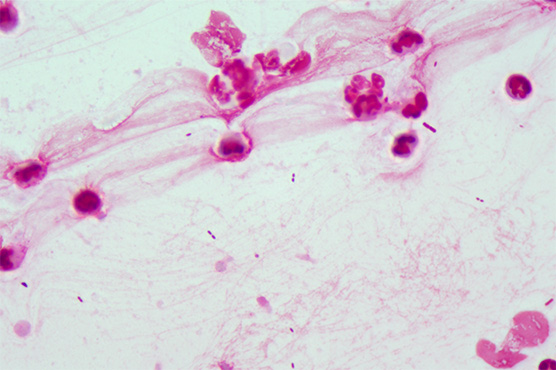

妇科真菌感染是目前比较常见的一种病症,妇科真菌感染对女性的的伤害也比较大。真菌适宜于在潮湿、温暖的环境繁殖;在有氧、温度合适、且有一定湿度的条件下,空气中飘散的真菌增多。深圳市妇幼保健院需要用到显微镜搭配显微镜相机来观看妇科白带涂片,从而对妇科真菌进行检查,从而进一步做诊断。

明美显微成像系统,包括明美显微镜相机及配套显微成像软件,可搭配不同品牌显微镜实时输出影像至屏幕,以了解对象状况,用作实时判断或记录。下图为明美显微镜相机MDX10搭配蔡司Axio Ascope显微镜拍摄妇科白带涂片。